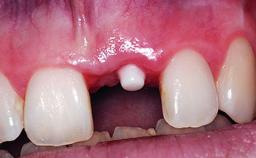

A healthy 37-year-old female patient was referred for a consultation on the replacement of missing tooth 21 with an implant-supported restoration. She stated that several years previously the tooth had been traumatically avulsed following a motor vehicle accident. The tooth was replaced with a three-unit fixed partial denture (FPD) immediately afterwards. Over time, she became disillusioned with the FPD and looked for a different option, including orthodontic therapy. She presented still in her orthodontic appliances, with the pontic sectioned free from the FPD but attached to the archwire. Her orthodontist felt that orthodontic treatment had been successfully completed, but nevertheless referred her before removing the appliances in case adjustments were necessary.

| Bone Augmentation | Horizontal|Simultaneous |

| Soft Tissue Grafting | Simultaneous |